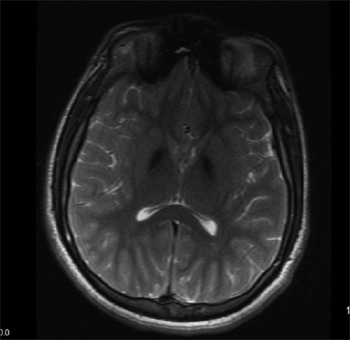

Mitochondrial membrane protein-associated neurodegeneration-Symmetric, hypointense lesions in the globus pallidus, and substantia nigra

MPAN might be suspected with typical presentation and findings on MRI (Magnetic Resonance Imaging), these include evidence of iron deposition in the brain, particularly in the basal ganglia (globus pallidus and substantia nigra).[1][3] The diagnosis is confirmed by genetic testing identifying harmful variant(s) in C19orf12.[1]